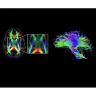

В системе SIGNA PET/MR есть все инструменты, необходимые для выявления маркеров разных заболеваний и для создания новых протоколов. ПЭТ/МРТ можно использовать совместно с мультиядерной спектроскопией в лаборатории in vivo для изучения быстрых биохимических процессов. Кроме того, PET ToolBox и набор инструментов Orchestra предоставляют персональный доступ к функциям реконструкции изображений для ПЭТ и МРТ, ускоряя и упрощая работу с необработанными данными.

• Специальный пакет приложений для измерения и сравнения объемных изображений ЦНС с нормами поможет вам в диагностике нейродегенеративных заболеваний, а дополнительные инструменты визуализации — в постановке точного диагноза с помощью бета-амилоидов и радиоизотопных маркеров ФДГ.

• In vivo лаборатория — получайте полные данные биохимических процессов in vivo с мультиядерной спектроскопией на SIGNA PET/MR.